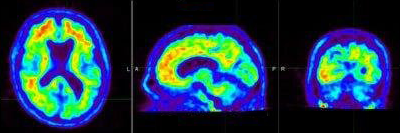

A Beta-Amyloid PET/CT scan will confirm deposits of Beta-Amyloid Plaque in the brain. This can help your neurologist determine whether or not you qualify for the new FDA approved treatment.

Positive Scan

Negative Scan